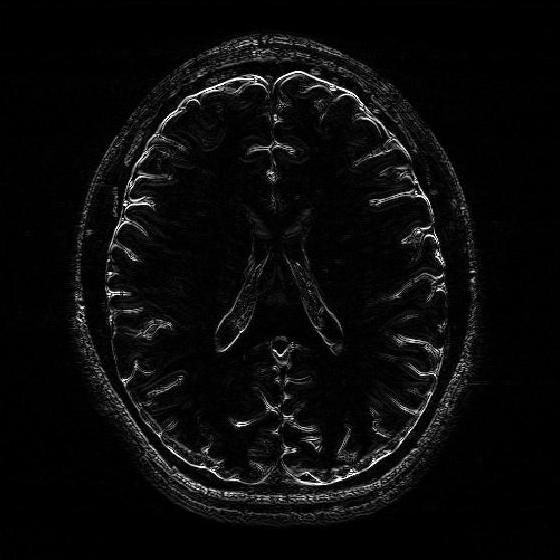

VII-D Application of the 2D-R-FFAST for MR imaging

Refer to caption

(a) Log intensity plot of the 2D-DFT of the original ‘Brain’ image. The red enclosed region is fully sampled and used for the stable inversion.

(b) Original ‘Brain’ image in spatial domain.

(c) Reconstructed ‘Brain’ image using the 2D-R-FFAST architecture along with the fully sampled center frequencies. The total number of Fourier measurements used is 60.18%percent60.1860.18\%.

(d) Log intensity plot of 2D-DFT of the original ‘Brain’ image, after application of the vertical difference operation.

(e) Differential ‘Brain’ image obtained using the vertical difference operation on the original ‘Brain’ image.

(f) Differential ‘Brain’ image reconstructed using the 2D-FFAST algorithm from 56.71%percent56.7156.71\% of Fourier measurements.

Figure 11: Application of the 2D-FFAST algorithm to reconstruct the ‘Brain’ image acquired on an MR scanner with dimension 504×504504504504\times 504. We first reconstruct the differential ‘Brain’ image shown in Fig. 11(e), using d=3𝑑3d=3 stage 2D-R-FFAST architecture with 151515 random delays in each of the 333 stages of the 2D-FFAST architecture. Additionally we acquire all the Fourier measurements from the center frequency as shown, by the red enclosure, in Fig. 11(a). Then, we do a stable inversion using the reconstructed differential ‘Brain’ image of Fig. 11(f) and the fully sampled center frequencies of Fig. 11(a), to get a reconstructed full ‘Brain’ image as shown in Fig. 11(c). Our proposed two-step acquisition and reconstruction procedure takes overall 60.18%percent60.1860.18\% of Fourier measurements.

In this section, we apply the 2D-R-FFAST algorithm to reconstruct a brain image acquired on an MR scanner with dimension 504×504504504504\times 504. In MR imaging the measurements are acquired in the Fourier domain and the task is to reconstruct the spatial image from significantly less number of Fourier measurements [17]. To reconstruct the full brain image using 2D-R-FFAST, we perform the following two-step procedure:

• Differential space signal acquisition: We perform a vertical finite difference operation on the image by multiplying the 2D-DFT signal with 1e2πıωx1superscript𝑒2𝜋italic-ısubscript𝜔𝑥1-e^{2\pi\imath\omega_{x}}. This operation effectively creates an approximately sparse differential image, as shown in Fig. 11(e), in spatial domain and can be reconstructed using 2D-FFAST. Note, that the finite difference operation can be performed on the sub-sampled data and at no point we access all the input Fourier measurements. The differential brain image is then sub-sampled and reconstructed using a 333 stage 2D-FFAST architecture. Also, since the brain image is approximately sparse, we take 151515 delay sub-streams in each of the 333 stages of the 2D-FFAST architecture, instead of 333 delay sub-streams as in the exactly sparse case. The 2D-R-FFAST algorithm reconstructs the differential brain image using 56.71%percent56.7156.71\% of Fourier measurements.

• Inversion using fully sampled center frequencies: After reconstructing the differential brain image, as shown in Fig. 11(f), we invert the finite difference operation by dividing the 2D-DFT measurements with 1e2πıωx1superscript𝑒2𝜋italic-ısubscript𝜔𝑥1-e^{2\pi\imath\omega_{x}}. Since the inversion is not stable near the center of the Fourier domain, only the non-center frequencies are inverted. The center region of the 2D-DFT is fully sampled and used in the inversion process.

• Overall we use a total of 60.18%percent60.1860.18\% of Fourier measurements to reconstruct the brain image using the 2D-R-FFAST algorithm along with the fully sampled center frequencies. The resulting signal-to-noise ratio of the reconstructed image is 4.51734.51734.5173 dB. While the reconstruction error is not as good as state-of-the-art compressed sensing MRI results, we note that the 2D-R-FFAST has both low computational complexity and low sample complexity , which none of the state-of-the-art compressed sensing results in MRI can achieve.